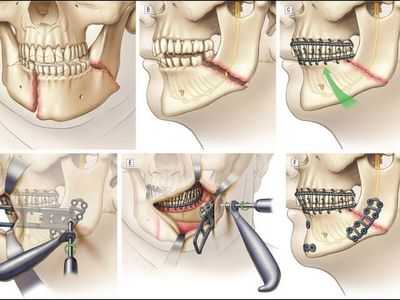

Лечение перелома нижней челюсти заключается в сопоставлении отломков и их фиксации. Иммобилизация обеспечивается проволочными назубными шинами, проволочными или полимерными нитями, остеосинтезом металлическими стержнями, а также с помощью специальных аппаратов. Раны ушивают, при обширных дефектах накладывают проволочные пластиночные швы. Важно обеспечить питание больного высококалорийной пищей, вводимой с помощью поильника или чайной ложки. Для предотвращения травматического остеомиелита вводят антибиотики.

Самым современным и адекватным методом лечения на данный момент является остеосинтез (фиксация титановыми накостными конструкциями) переломов верхней челюсти. Это хирургическое вмешательство, выполняемое из внутриротовых разрезов. При таком варианте лечения можно точно сопоставить и зафиксировать фрагменты для создания условий их сращения [7] .

При ангулярных травмах со смещением требуется наложение костного шва. Для этого трещину обнажают от мягких тканей, во фрагментах кости делают небольшие отверстия по всей длине разлома. Затем части соединяют между собой специальной проволокой и закрывают мягкой тканью.

Лечение заключается в сопоставлении отломков и их фиксации. Иммобилизация обеспечивается проволочными назубными шинами, проволочными или полимерными нитями, остеосинтезом металлическими стержнями, а также с помощью специальных аппаратов (Рудько, Збаржа). Раны ушивают, при обширных дефектах накладывают проволочные пластиночные швы. Неотложная помощь состоит из транспортной иммобилизации, остановки кровотечения, предупреждения асфиксии и противошоковых мероприятий. Транспортную иммобилизацию производят жесткой подбородочной пращевидной повязкой. Для предупреждения асфиксии больного усаживают либо укладывают на бок. Если язык западает, то его прошивают лигатурой и фиксируют. При необходимости производят трахеотомию. Важно обеспечить питание больного жидкой высококалорийной пищей, вводимой с помощью поильника либо чайной ложки. Для предотвращения развития травматического остеомиелита вводят антибиотики.